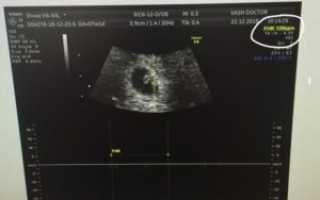

УЗИ — беременность двойней 7 акушерских недель

Также снимок УЗИ укажет на количество эмбрионов: покажет, сколько детей ожидается у беременной — один, двойня или больше. Стоимость процедуры составляет 2400 рублей.